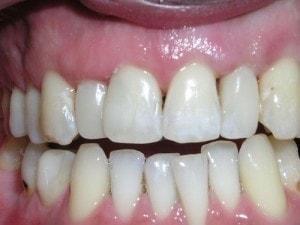

Completed restorations

-

Completed #7 composite Build Up

Incisal view #7

Connect